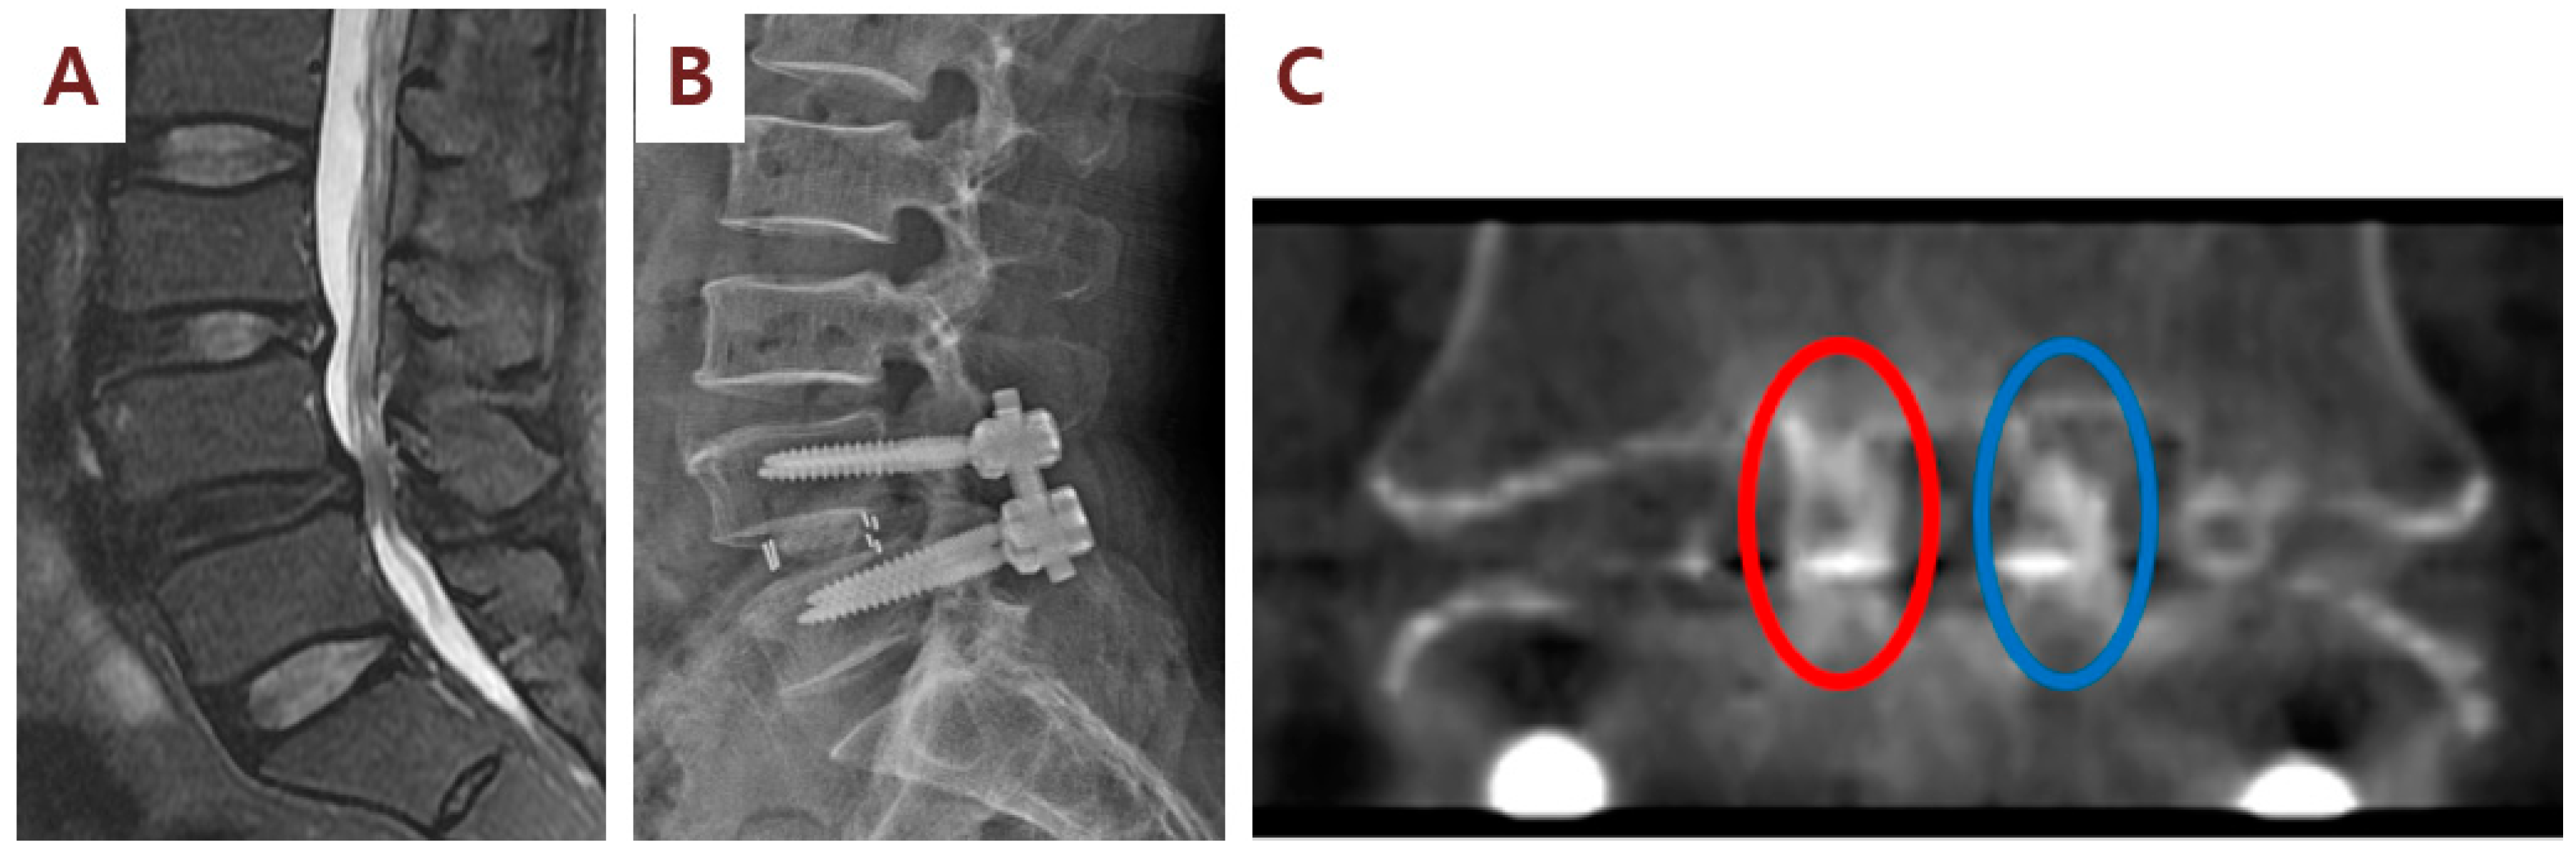

3.2. Clinical and Radiographic Outcomes